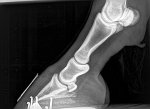

The x rays have been sent over to me. These are her front feet.

Wow that pedal bone is so close to the sole.... the toes are very long - even a trim to shorten the toe will help but a whole resection is completely unneccessary. Have you called a podiatrist?

she is due her trim this week. I don’t mean to come across rude now I’m genuinely intrigued, (it’s hard to tell tone over the internet!)when you say it’s unnecessary why would a vet suggest this? I feel like if they take the shoe off they may find more that they’re hoping to with that pedal bone. I do wonder how this resection even works, I know it relieves the pressure but how can this kind of rotation be rectified with such a procedure? The vet explained it’s the pressure releasing and then she’ll be in less pain thus being able to heal better but for me that bone is so far rotated I can’t see a way back

hooves grow, so if you manage to resolve the cause of the laminitis you can grow a tighter connection back down and the pedal bone has the potential to end up back where it should be.

The trouble being that hooves take a fair time to grow, and sometimes don't always grow in helpful directions.